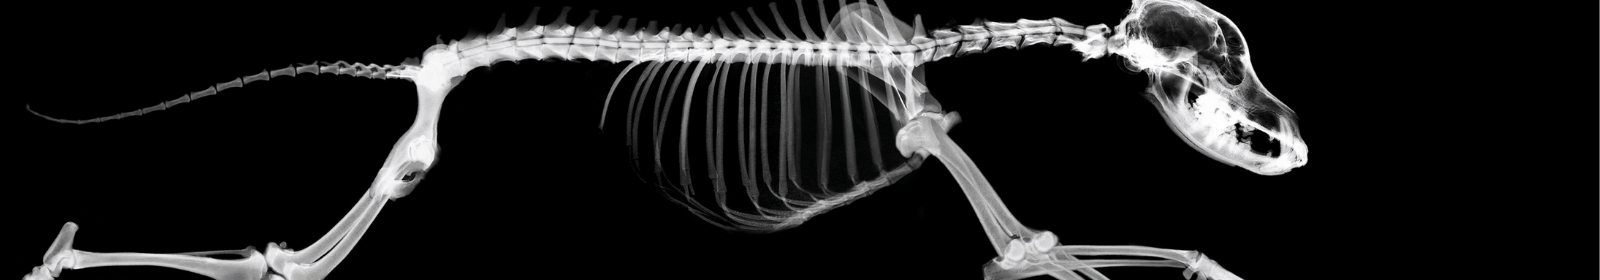

Radiologia – estudos radiográficos aplicados à ortopedia e coluna vertebral

Tomografia computadorizada e sua aplicação na ortopedia, coluna vertebral e medula espinhal

Ressonância magnética e sua aplicação na ortopedia, coluna vertebral e medula espinhal